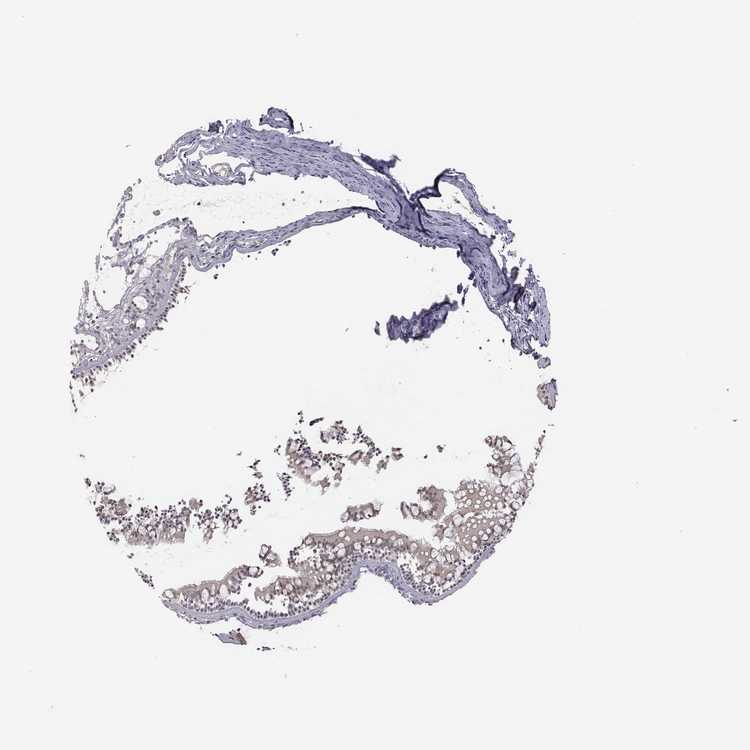

NASOPHARYNX - Antibody stainingi

Antibody staining in the annotated cell types in the current human tissue is reported as not detected, low, medium, or high, based on conventional immunohistochemistry profiling in selected tissues. This score is based on the combination of the staining intensity and fraction of stained cells.

Each image is clickable and will lead to virtual microscopy that enables deeper exploration of all samples and also displays staining intensity scores, fraction scores and subcellular localization as well as patient and tissue information for each sample.

Antibody HPA071508

Respiratory epithelial cells Not detected